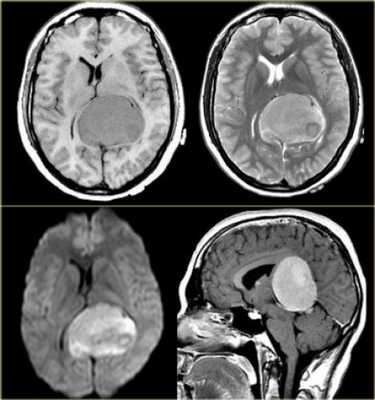

Пинеоцитома - доброкачественная опухоль, возникающая из ткани шишковидной железы, имеющая четкие контуры (рис.724, 725).

Пинеоцитома - доброкачественная опухоль, происходящая из паренхимы corpus pineale, хорошо ограниченное, инкапсулированное, медленно растущее, неинвазивное поражение. Опухоль может содержать кальцинаты по периферии [137]. Размеры образования могут быть различны, но это не связано с атипией опухоли. На КТ пинеоцитомы были описаны как → или слегка ↑, на МРТ это солидная фракция описывается, как ↓T1 и →Т2 [137].

Объёмное образование шишковидной железы, представленное мягкотканным образованием с наличием капсулы (стрелки на рис.729, 730). Пинеоцитома может иметь кисты (головка стрелки на рис.728).

Контрастное усиление

На КТ и МРТ солидные компоненты интенсивно накапливают контраст [34,43,49,53,130].

Интенсивное контрастирование солидных участков пинеоцитомы (стрелки на рис.731-733).